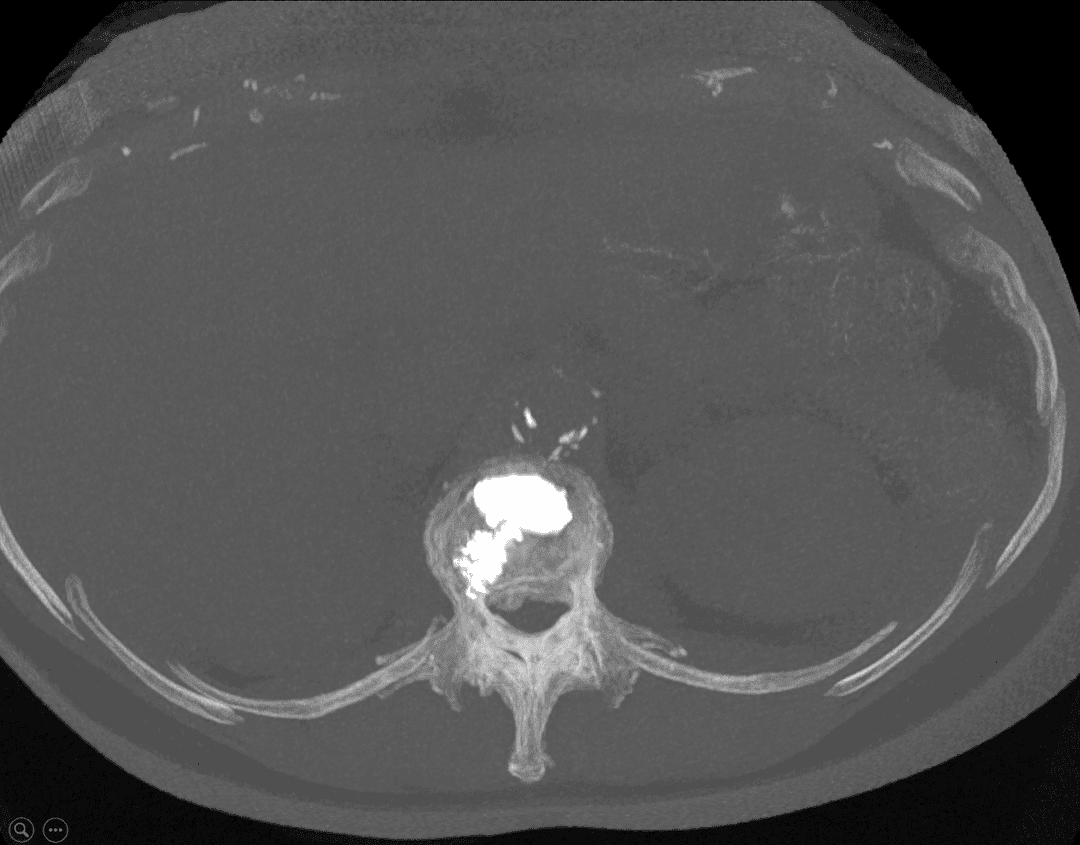

Scanner montrant une fracture d'une vertèbre

Résultat après injection de ciment